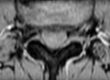

Nell’immagine possiamo notare come nelle immagini superiori che hanno strati più sottili, si possono visualizzare piccole alterazioni a livello dei corpi vertebrali che nelle immagini sottostanti più spesse non sono più visibili.